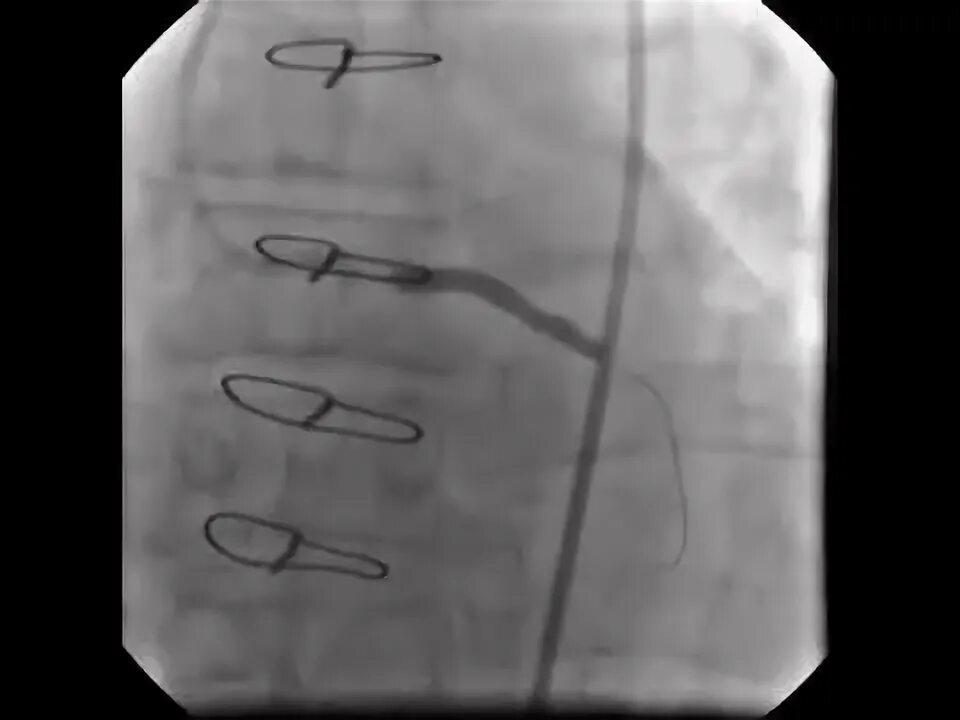

Стентирование самолет